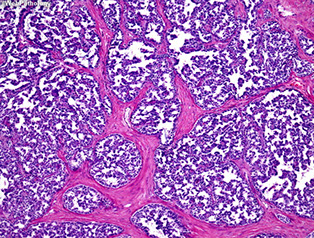

Well-differentiated Neuroendocrine tumors (carcinoid tumors) and other neuroendocrine tumors

Historically known as Carcinoid tumors; they  arise from the enterochromaffin-like (ECL) cells throughout the gut

- carcinoid really must have production of serotonin, and cause carcinoid syndrome

- collections of NE cells <0.5 mm known as NeuroEndocrine (NE) cell hyperplasia

- Micro-NE tumors are those 0.5 to 5 mm that are not identified endoscopically

Types:

- classified into several type:

(1) ECL tumors assoc c chronic atrophic gastritis, type A

(2) ECL tumors assoc c ZE syndrome or MEN1 (and hypergastrin secretion from gastrinoma)

(3) sporadic ECL lesions (w/o hypergastrinemia)

(4) Non-ECL tumors

(5) ECL cell tumor c achlorhydria and parietal cell hyperplasia

- autoimmune atrophic gastritis (abs against parietal cells) causes loss of oxyntic glands and mucosal atrophy, causing dec HCl production and hyperproduction of gastrin by antral G cells, causing tumors that can be multifocal

- type 3 (sporadic) lesions are more aggressive, req aggressive surgery

- all have small round proliferating cells

- confirm c NE stains

- graded c mits and Ki67 ([1] = <2 mits/hps or <2% Ki67; [2] = 2-20 mits /hpf or 3-20% Ki67; [3] = HG NE Ca c >20 mits/hpf or Ki67>20%)

1) Well-differentiated NeuroEndocrine Tumors (WDNETs)

- aka NeuroEndocrine Tumors Grade 1 (NET G1)

MCC, originate from ECL cells

Gastric carcinoid tumors / appendix[?]

Well-diff NE tumor

Carcinoid with nesting, rosetting, and pseudoalveolar forms